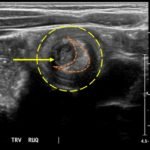

The patient’s abdominal ultrasound revealed intussusception in the right upper abdominal quadrant. The transverse ultrasound view showed a “doughnut sign” (dashed yellow line), telescoping bowel (yellow arrow), and invaginated hyperechoic mesenteric fat with crescent configuration (dashed orange line). The sagittal ultrasound view demonstrated the intussusception formed by the outer recipient bowel loop (yellow arrows), invaginated hyperechoic mesenteric fat (orange asterisks), and telescoping bowel centrally (red arrow).

Ultrasonography should be the initial imaging modality in cases with clinical suspicion for intussusception.4 Previously, contrast enemas were often used as a diagnostic tool and treatment modality. Studies have demonstrated that the modality choice had been related to age, with infants less than six months more likely to undergo enema while children greater than four were more likely to have a computed tomography scan or ultrasound.5 In the pediatric population, ultrasound has a sensitivity of 97.9% and specificity of 97.8% for diagnosis of ileocolic intussusception.6 A “doughnut,” “pseudokidney,” or “target sign” are diagnostic findings.3,7 The study could be performed by radiology or at the bedside in the ED.8,9 A study reported that with limited training, ED physicians could accurately perform ultrasound to diagnose intussusception, with a sensitivity of 85% and a specificity of 97%. Further studies are needed to determine the utility of bedside ultrasound for the diagnosis of intussusception in the community setting.3